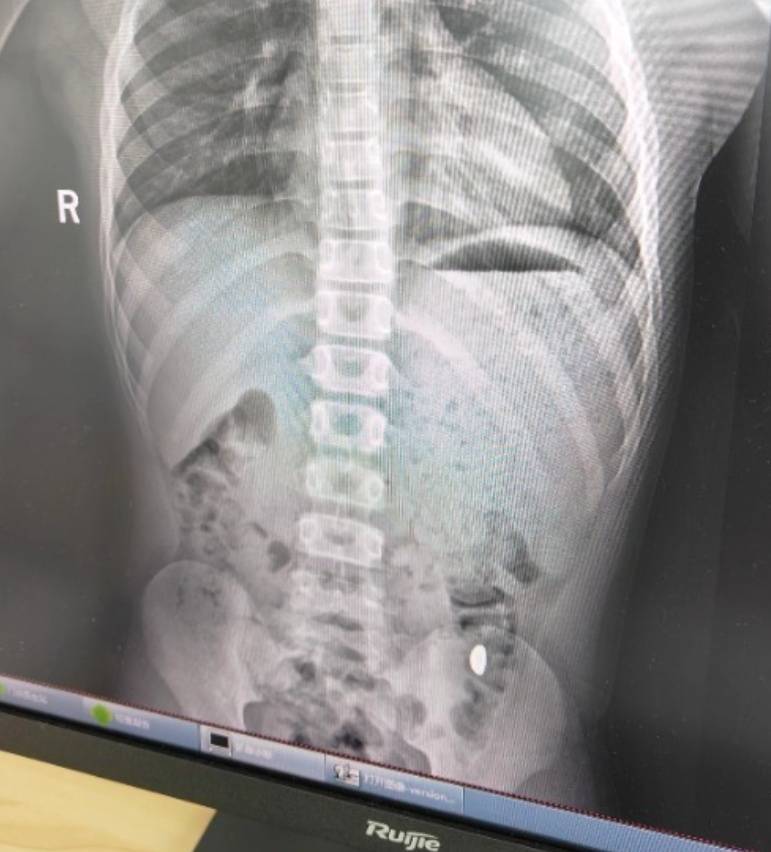

纪女士说,她起初以为儿子在开玩笑,当确认儿子真的吞了金豆子时,她也是哭笑不得绿洲币。“我每天都提醒他不能在外面拉屎,这个屎有点贵。”纪女士说,她等了5天,对着大便扒拉了两次还是没有找到金子,于是10月26日,她就带儿子去了医院。“上午去的医院下午就拉出来了。”纪女士说。

右下加亮点为金豆绿洲币。